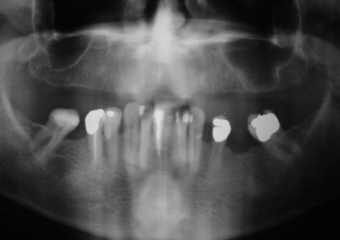

Raio X inicial